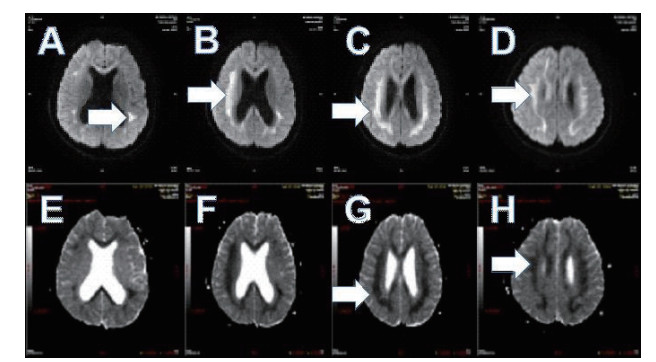

2 结果 2.1 基本资料及头颅核磁特征本观察研究最终纳入患者51例,中毒患者的头颅核磁特征表现为:在MRI的常规序列(T1\T2\FLAIR)病灶显示不明显,但在DWI表现为高信号,ADC值下降呈低信号。病变部位主要是胼胝体的压部(所有阳性病例胼胝体压部均受损),病变也可以形成以胼胝体为中心的广泛白质病变,皮质不受损害。见图 1,2。

| 图 1 A.T1序列/B.T2序列/C.FLAIR序列均无异常;D.DWI系列上为高信号(箭头所示) |

| 图 2 A\C弥散像呈高信号,B\D ADC图呈低信号(箭头所示) |